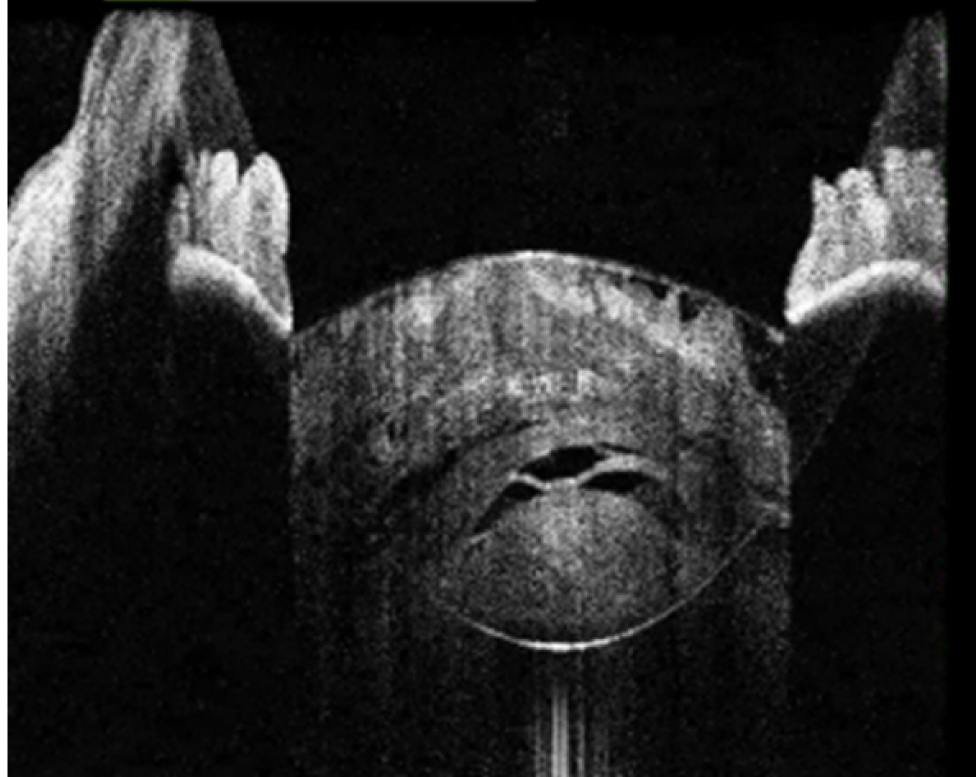

Рис. 3. Тип 3 перезрелой катаракты: выпуклая передняя капсула хрусталика, гиперрефлективные полосы набухших кортикальных волокон, внутрихрусталиковые щели, области однородного вида «матового стекла»

Рис. 4. Тип 4 перезрелой катаракты: гомогенные передние кортикальные слои хрусталика вида «матового стекла»